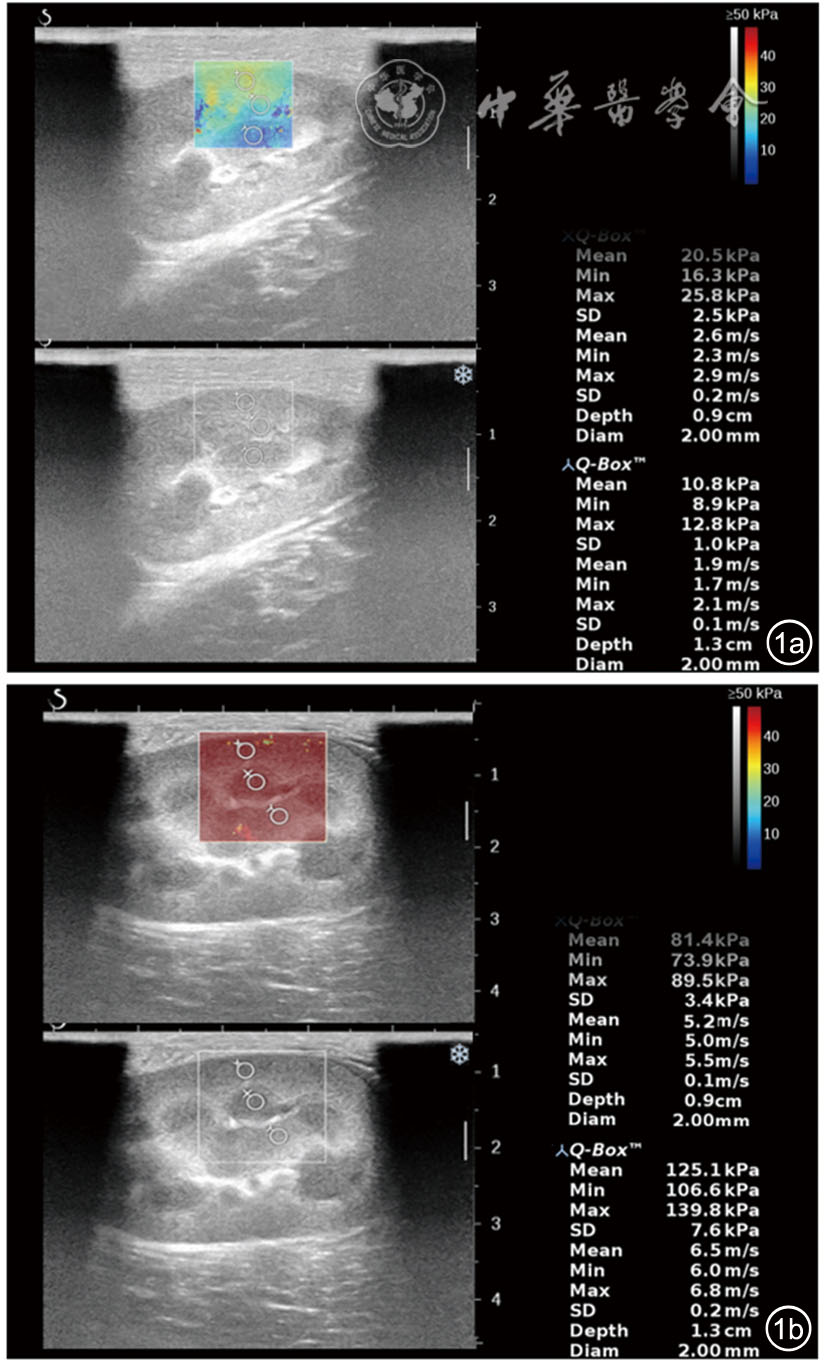

A total of 20 New Zealand White rabbits were used as the study subjects. At 2 hours after ligation of the left renal vein, Young's modulus was measured and compared across different sides (healthy side vs affected side), anatomical locations (upper pole vs mid portion vs lower pole), and organizational structures (cortex vs medulla vs renal sinus) of the kidney. The point-biserial correlation coefficient was employed to analyze the correlation between Young's modulus in various renal regions and the status of acute renal vein occlusion. The intraclass correlation coefficient (ICC) was used to assess the reproducibility of the Young's modulus measurements.

Regarding anatomical locations, in the healthy side group, the differences in Young's modulus were statistically significant between the upper pole and mid portion, and between the mid portion and lower pole (P<0.05). In the affected side group, no statistically significant differences in Young's modulus were observed among the upper pole, mid portion, and lower pole (P>0.05). Regarding organizational structures, in the healthy side group, the differences in Young's modulus were statistically significant between the cortex and renal sinus, and between the medulla and renal sinus (P<0.05). In the affected side group, the differences in Young's modulus among the cortex, medulla, and renal sinus were all statistically significant (P<0.05). Three-way ANOVA revealed that the three-way interaction effect (acute renal vein occlusion status × anatomical location × organizational structure) was not statistically significant (F=1.575, P=0.190). The Young's modulus values in the affected side group were consistently higher than those in the healthy side group for identical anatomical locations and organizational structures, and all these differences were statistically significant (P<0.05). Among these comparisons, the mid-portion cortex demonstrated the most prominent effect size (Cohen's d=2.770), eexhibited the strongest correlation with acute renal vein occlusion (r=0.867), and showed the optimal measurement reproducibility (ICC=0.987).